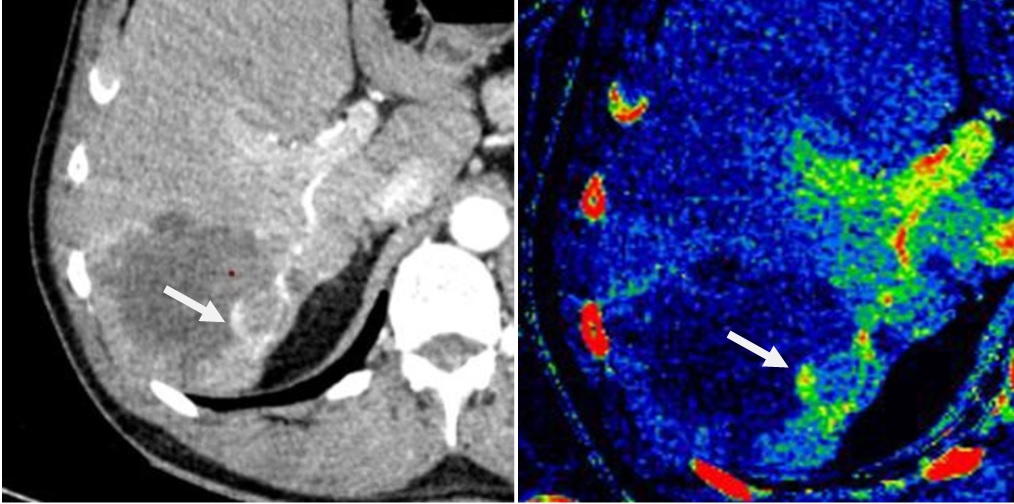

- Công nghệ GSI Xtream, công nghệ chụp cắt lớp vi tính phổ theo thể tích đầu tiên với khả năng chuyển đổi mức năng lượng cực nhanh, được thiết kế để tăng cường khả năng phát hiện những tổn thương nhỏ, xác định đặc điểm mô, giảm nhiễu ảnh kim loại. Chụp cắt lớp vi tính phổ được ứng dụng trong việc phát hiện và theo dõi các tổn thương gan, phân biệt các loại sỏi tiết niệu, đánh giá sau đặt coil mạch não, stent graft, các khớp nhân tạo, sau đặt nẹp vít cột sống, đánh giá mức độ phù tủy xương, phát hiện và đánh giá bệnh Gút, chụp tưới máu cơ tim,...

Hình 3. Hình ảnh chụp CLVT 512 dãy phổ theo dõi tổn thương mới sau Hubet6677 phiên bản mới đốt nhiệt cao tần tổn thương di căn gan